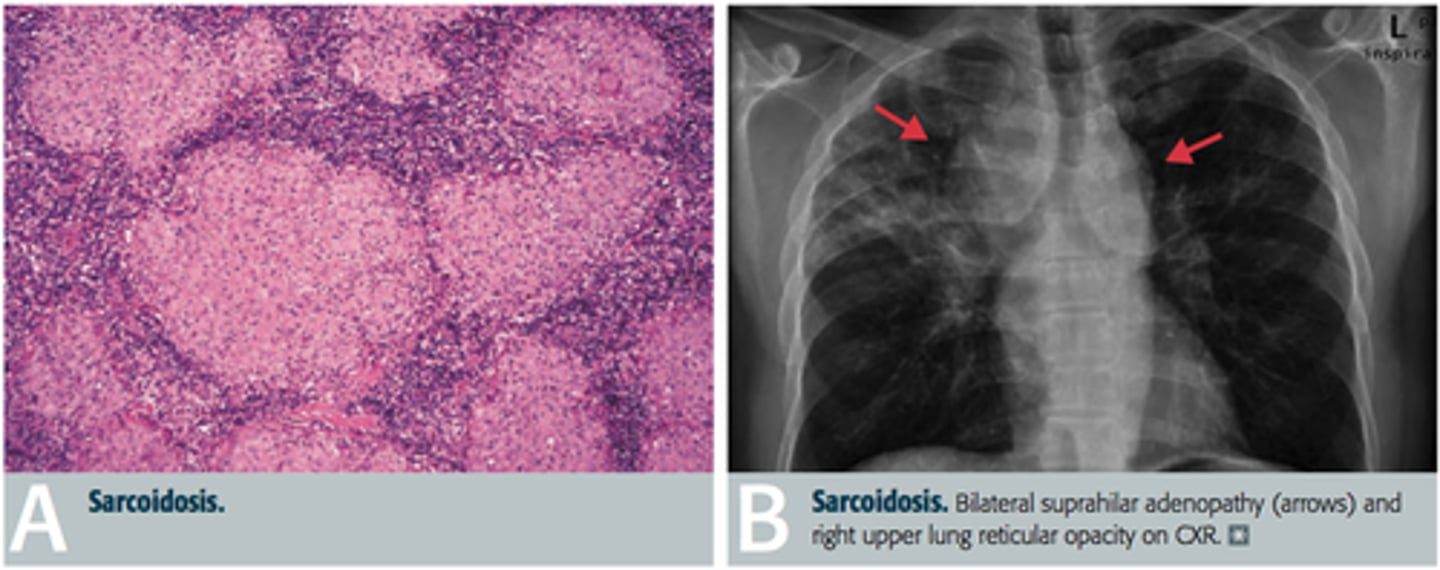

Bilateral hilar adenopathy, uveitis, high ACE, hypercalcemia (activated macrophages for Vit D), interstitial fibrosis, erythema nodosum, high CD4

Sarcoidosis (non-caseating granulomas)